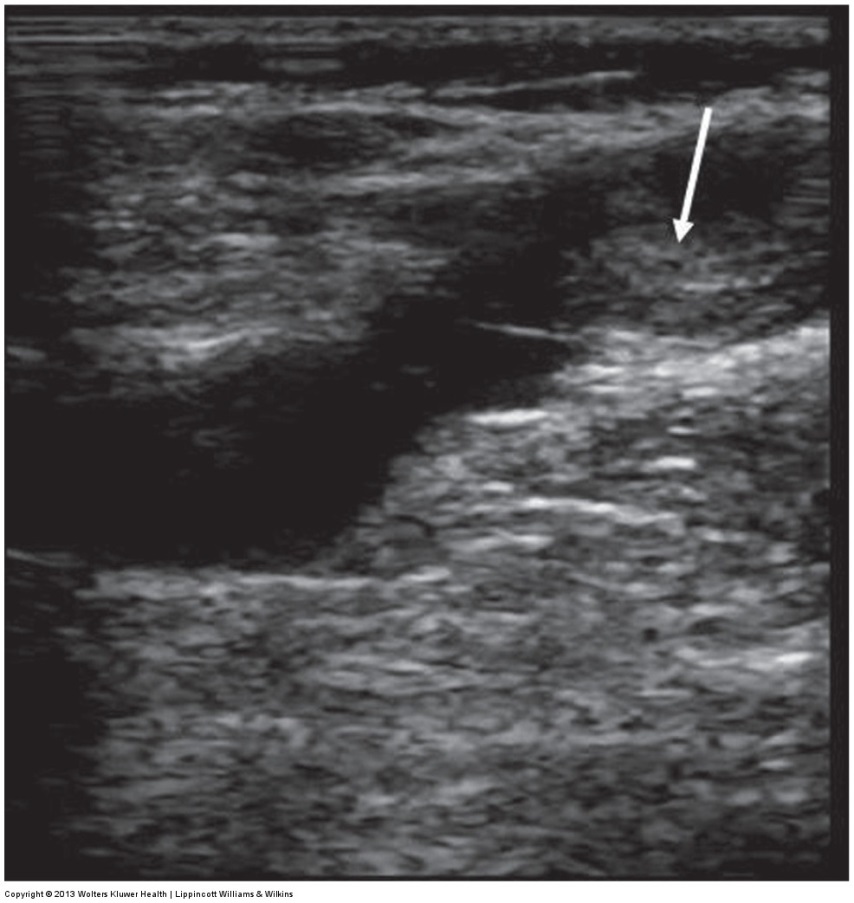

ultrasound image of thrombus next to valve leaflets